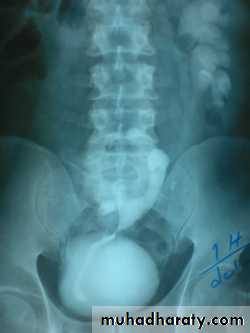

IVU

Large kidney .

Lobulated out-line.

Distortion of pelvi- calyceal system depend on cyst size, number and position.

In advanced cases there is elongation and stretching of minor and major calyces ( spider leg).

In advanced cases IVU shows non-functioning kidney .